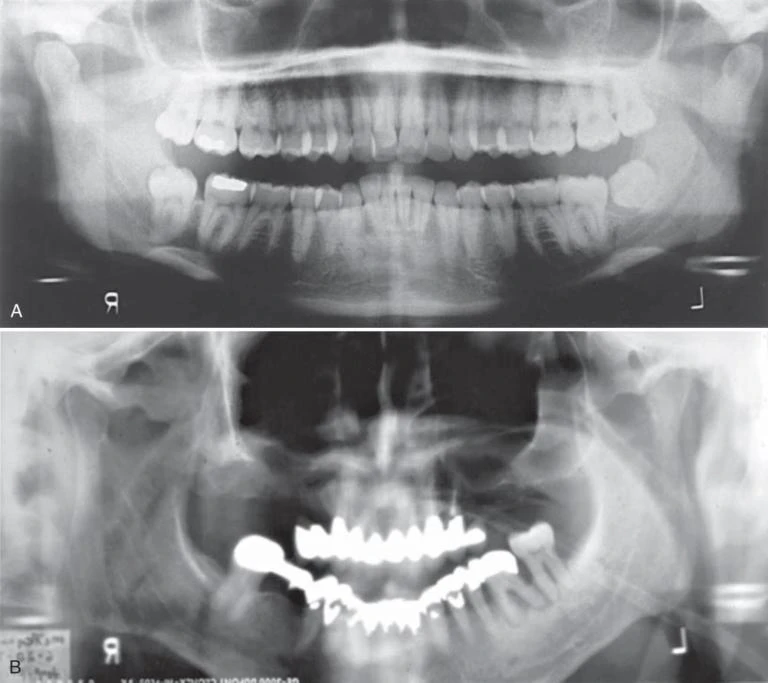

Vị trí bệnh nhân quá xa về phía trước hoặc phía sau đều dẫn đến sai lệch về kích thước hình ảnh nghiêm trọng. Quá xa về phía sau dẫn đến phóng đại kích thước gần xa ở đoạn phía trước và dẫn đến làm răng bị “mập”. Quá xa về phía trước dẫn đến giảm kích thước gần xa ở phân đoạn răng trước dẫn đến răng “gầy”. Đặt vị trí mặt phẳng dọc giữa sai so với đường giữa của máy X quang dẫn đến hình ảnh bên phải và bên trái có độ phóng đại không bằng nhau theo chiều ngang. Chọn vị trí đường giữa sai là một lỗi phổ biến, dẫn đến biến dạng hình ảnh theo chiều ngang ở vùng răng sau, chồng hình ảnh răng ở vùng răng cối nhỏ và đôi khi không thể chẩn đoán được, trên lâm sàng đây là một hình ảnh không thể chấp nhận được. Một phương pháp đơn giản để đánh giá mức độ biến dạng theo chiều ngang của hình ảnh là so sánh độ rộng của răng cối lớn thứ nhất hàm dưới ở hai bên. Bên nhỏ hơn là quá gần với receptor và bên lớn hơn quá gần với nguồn tia X. Cằm của bệnh nhân và mặt phẳng nhai phải nằm ở vị trí đúng để tránh biến dạng hình. Mặt phẳng nhai được sắp sao cho nó thấp hơn về phía trước, tạo góc từ 20 đến 30 độ dưới đường nằm ngang. Một hướng dẫn chung đối với vị trí của cằm là đặt bệnh nhân sao cho một đường từ vành tai đến khóe ngoài của mắt song song với sàn nhà. Nếu cằm nghiêng quá cao, mặt phẳng nhai trên phim sẽ phẳng hoặc cong ngược, và hình ảnh xương hàm dưới bị biến dạng. Ngoài ra, một bóng cản quang của khẩu cái cứng chồng lên các chân răng hàm trên. Nếu cằm nghiêng quá thấp, răng bị chồng lên nhau nghiêm trọng, khu vực xương hàm dưới có thể bị mất ở trên phim, và cả lồi cầu xương hàm dưới có thể nằm ra ngoài cạnh trên của phim. Bệnh nhân có vị trí sao cho lưng của họ và xương sống càng thẳng với cổ càng tốt. Hướng dẫn bệnh nhân đứng trên tấm lót chân và sử dụng nệm để hỗ trợ phần lưng có thể giúp định vị vị trí lưng đúng một cách dễ dàng trong trường hợp ngồi chụp. Những thiết bị này giúp làm thẳng đốt sống, giảm tối thiểu hình ảnh giả do bóng của cột sống.